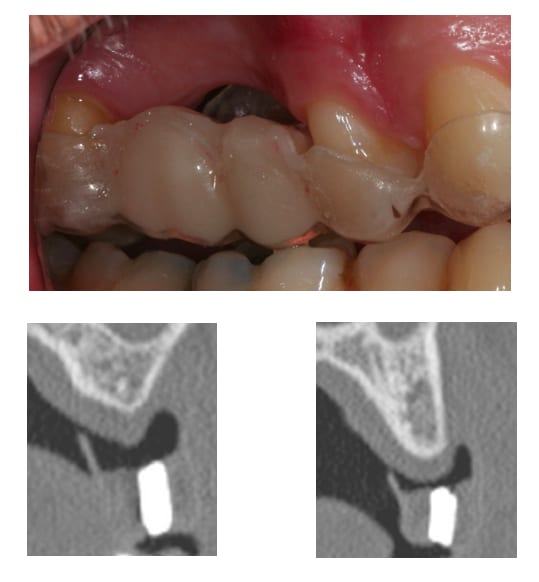

> en haut, comment vas-tu gérer les concavités de la crête? greffes?

il est prévu de faire une ROG.

simultanée avec Bio-Oss et os autogène.

oui membrane Bio-Gide en double épaisseur, avec rien.

avec Bio-Oss, os autogène et Bio-Gide et pose d'implant simultanée, peut être les photos le mois prochain.